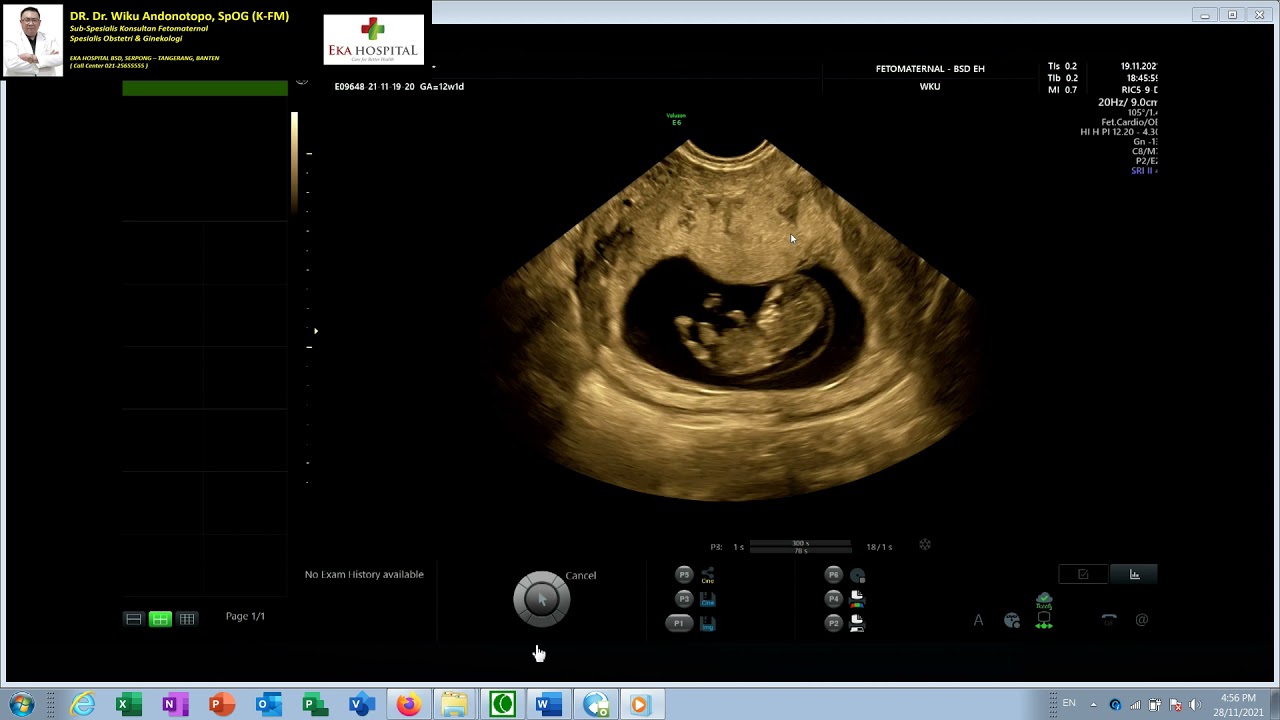

TRISOMI 21 - NUCHAL EDEMA TEBAL - HYDROPS FETALIS  12 WEEKS (Dr Wiku Andonotopo)

DR. Dr. Wiku Andonotopo, SpOG (K-FM)

Sub-Spesialis Konsultan Fetomaternal

Spesialis OBSGYN

Eka Hospital, Fetomaternal Diagnostic Clinic, BSD, Serpong, Banten (021-25655555)